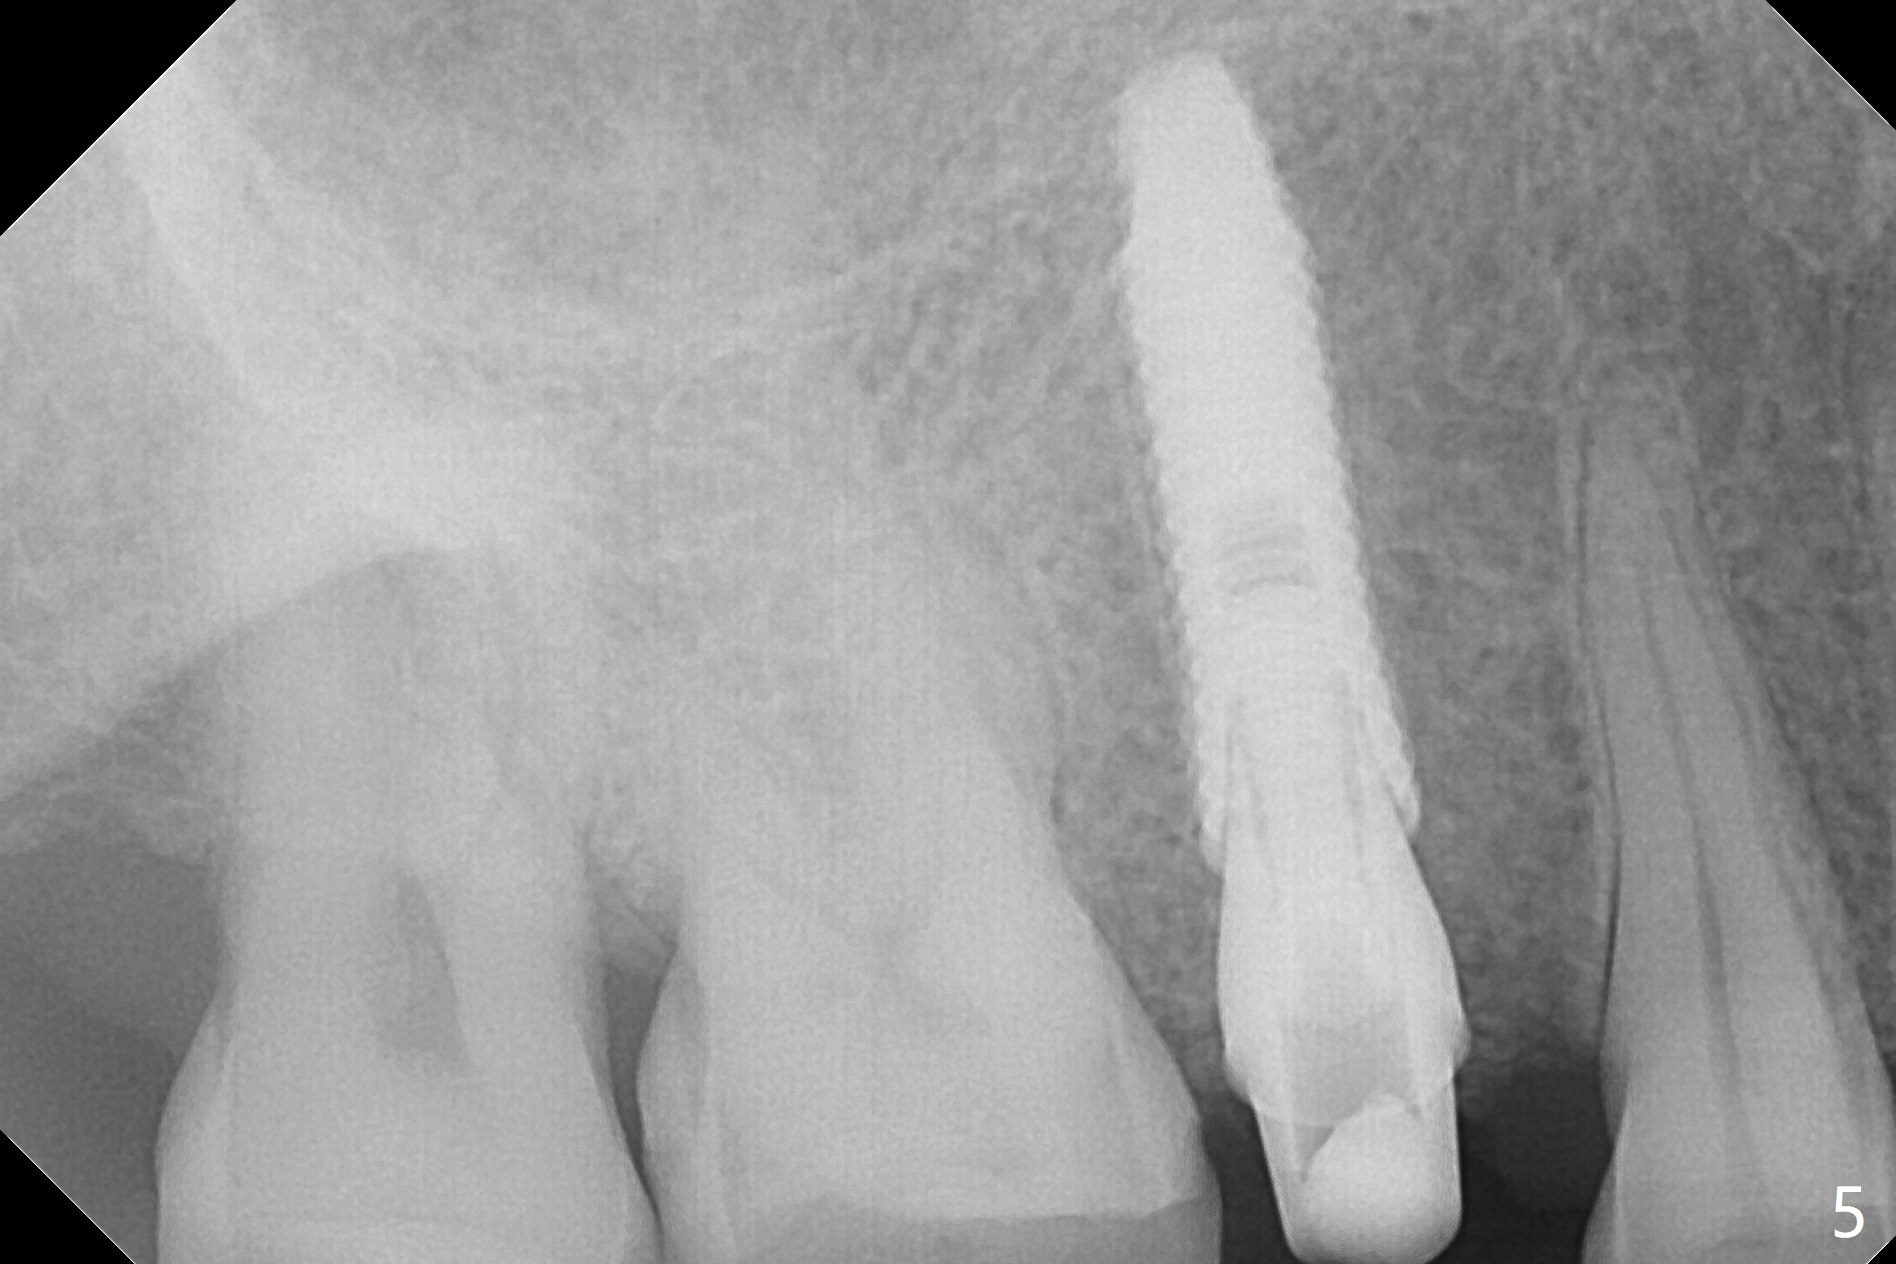

After sequential osteotomy, a 4x16 mm implant is initially unable to be seated low enough for the buccal crest.  Following packing the osteotomy with Vanilla Graft (.5-1 mm) and additional 2-3 mm depth of osteotomy with 3 mm reamer, the implant is placed slightly apical to the buccal crest (Fig.4,5, ~35 Ncm); with placement of Vanilla Graft (*) and a 4.5x4(4) mm abutment, an immediate provisional is fabricated to close the socket.  In fact the long implant has not penetrated the sinus floor (Fig.8 (from panoramic X-ray)).